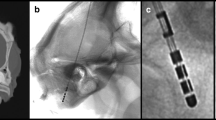

Explanation of “iron sight” in X-ray in reference to the frame and ACPC line. A Schematic drawing of a directional lead in reference to the ACPC line (green) and X-ray beam (yellow), which is perpendicular to the frame anterior-posterior axis (red). B Appearance of an “iron sight” every 60° on a schematic drawing of a directional lead. C “Iron sight” on intraoperative X-ray when the radiation beam traverses the frame laterally at a 90° angle. Abbreviations: ACPC, anterior commissure–posterior commissure. Figure was created using Procreate® on an iPad Pro (Apple®) and power point (Microsoft®)

The two last X-rays, one after locking the lead (i.e., “pre-final X-ray”; Supplementary Fig. 1A) and one after fixating the lead (i.e., “final X-ray”; Supplementary Fig. 1D), were analyzed. D-lead orientation was determined by the ISi method as previously described [7]. In brief, when a radiation beam traverses a d-lead from the side at a 90° angle, an ISi becomes visible every 60° (360°/6) (Fig. 1). When the marker is facing strictly anterior and the ISi is perfectly visible, the rotation of the lead can be regarded as 0°. To be precise, due to the d-lead dimensions, oblique lead angles, and conventional X-ray resolution, we observed the gap to be visible over a range of approximately 12° (i.e., − 6 to + 6°) (Fig. 2).